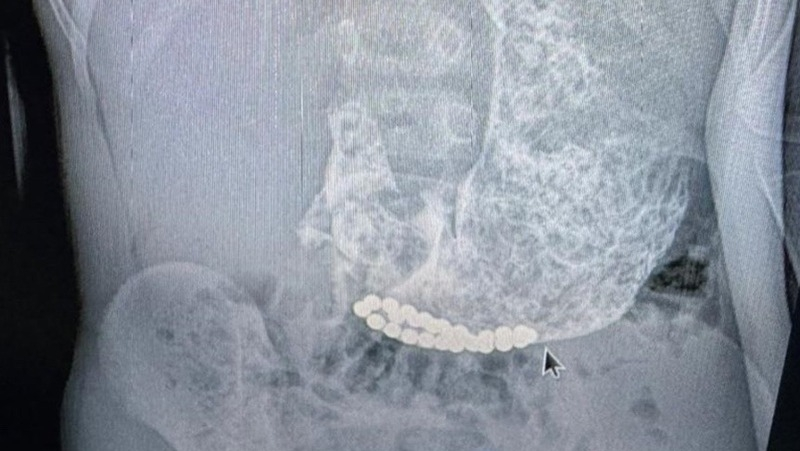

Третьего малыша пришлось прооперировать. У него наблюдалась многократная рвота, и родители обратились к врачу по месту жительства. Медики выяснили, что в тонком кишечнике ребёнка находятся инородные тела — магниты.

Пациента отправили в детскую крайбольницу, где экстренно прооперировали. Во время хирургического вмешательства врачи выявили кишечную непроходимость из-за сращения кишечных петель — они притягивались друг к другу магнитами. Операция прошла успешно, ребёнок продолжает проходить лечение.